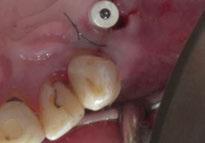

Para ilustrar el proceso, presentamos el caso de una mujer joven diagnosticada de carcinoma adenoide quístico en la región posterior del hemipaladar izquierdo (Figuras 1 y 2). El procedimiento quirúrgico realizado fue una

maxilectomía parcial que incluyó las piezas 24-26 y desde el reborde alveolar hasta la base del cráneo (Figuras 3 y 4). En este caso, la órbita y el globo ocular pudieron ser preservados. La reconstrucción inmediata se realizó mediante un colgajo de músculo temporal homolateral (Figura 5) y el defecto de la fosa temporal fue cubierto mediante una malla de titanio. Posteriormente, la paciente recibió radioterapia (Figuras 6 y 7). 2 años más tarde se diseñó un IS con anclaje en el arbotante nasomaxilar, zona subnasal izquierda

Figura 1. Imagen preoperatoria de la paciente.

Figura 2. Carcinoma adenoide quístico en región posterior del hemimaxilar izquierdo.

Figura 3. Maxilectomía parcial.

Figura 4. Defecto maxilar tras resección del tumor.

y lo que se pudo preservar del hueso malar. Se añadió una malla sinterizada infraorbitaria para dar volumen a la mejilla y se planificaron dos brazos de conexión que emergieran en las posiciones 24 y 26 de forma subgingival (Figuras 8 y 9). La superficie interna que apoyaba en el hueso era de titanio microrrugoso, y la superficie externa y conectores de titanio pulido y hexágono externo universal (Figuras 10 y 11). La cirugía se hizo bajo anestesia general en infiltración con anestesia local (4% articaína, 1:100.00 epinefrina), levantando el

colgajo cutáneo de la mejilla por vía intraoral, preservando el colgajo temporal para no comunicar con el remanente de la cavidad naso maxilar (Figura 12). Se emplearon 10 tornillos de osteosíntesis de 1,9 mm y la estabilidad primaria obtenida fue excelente (Figura 13)